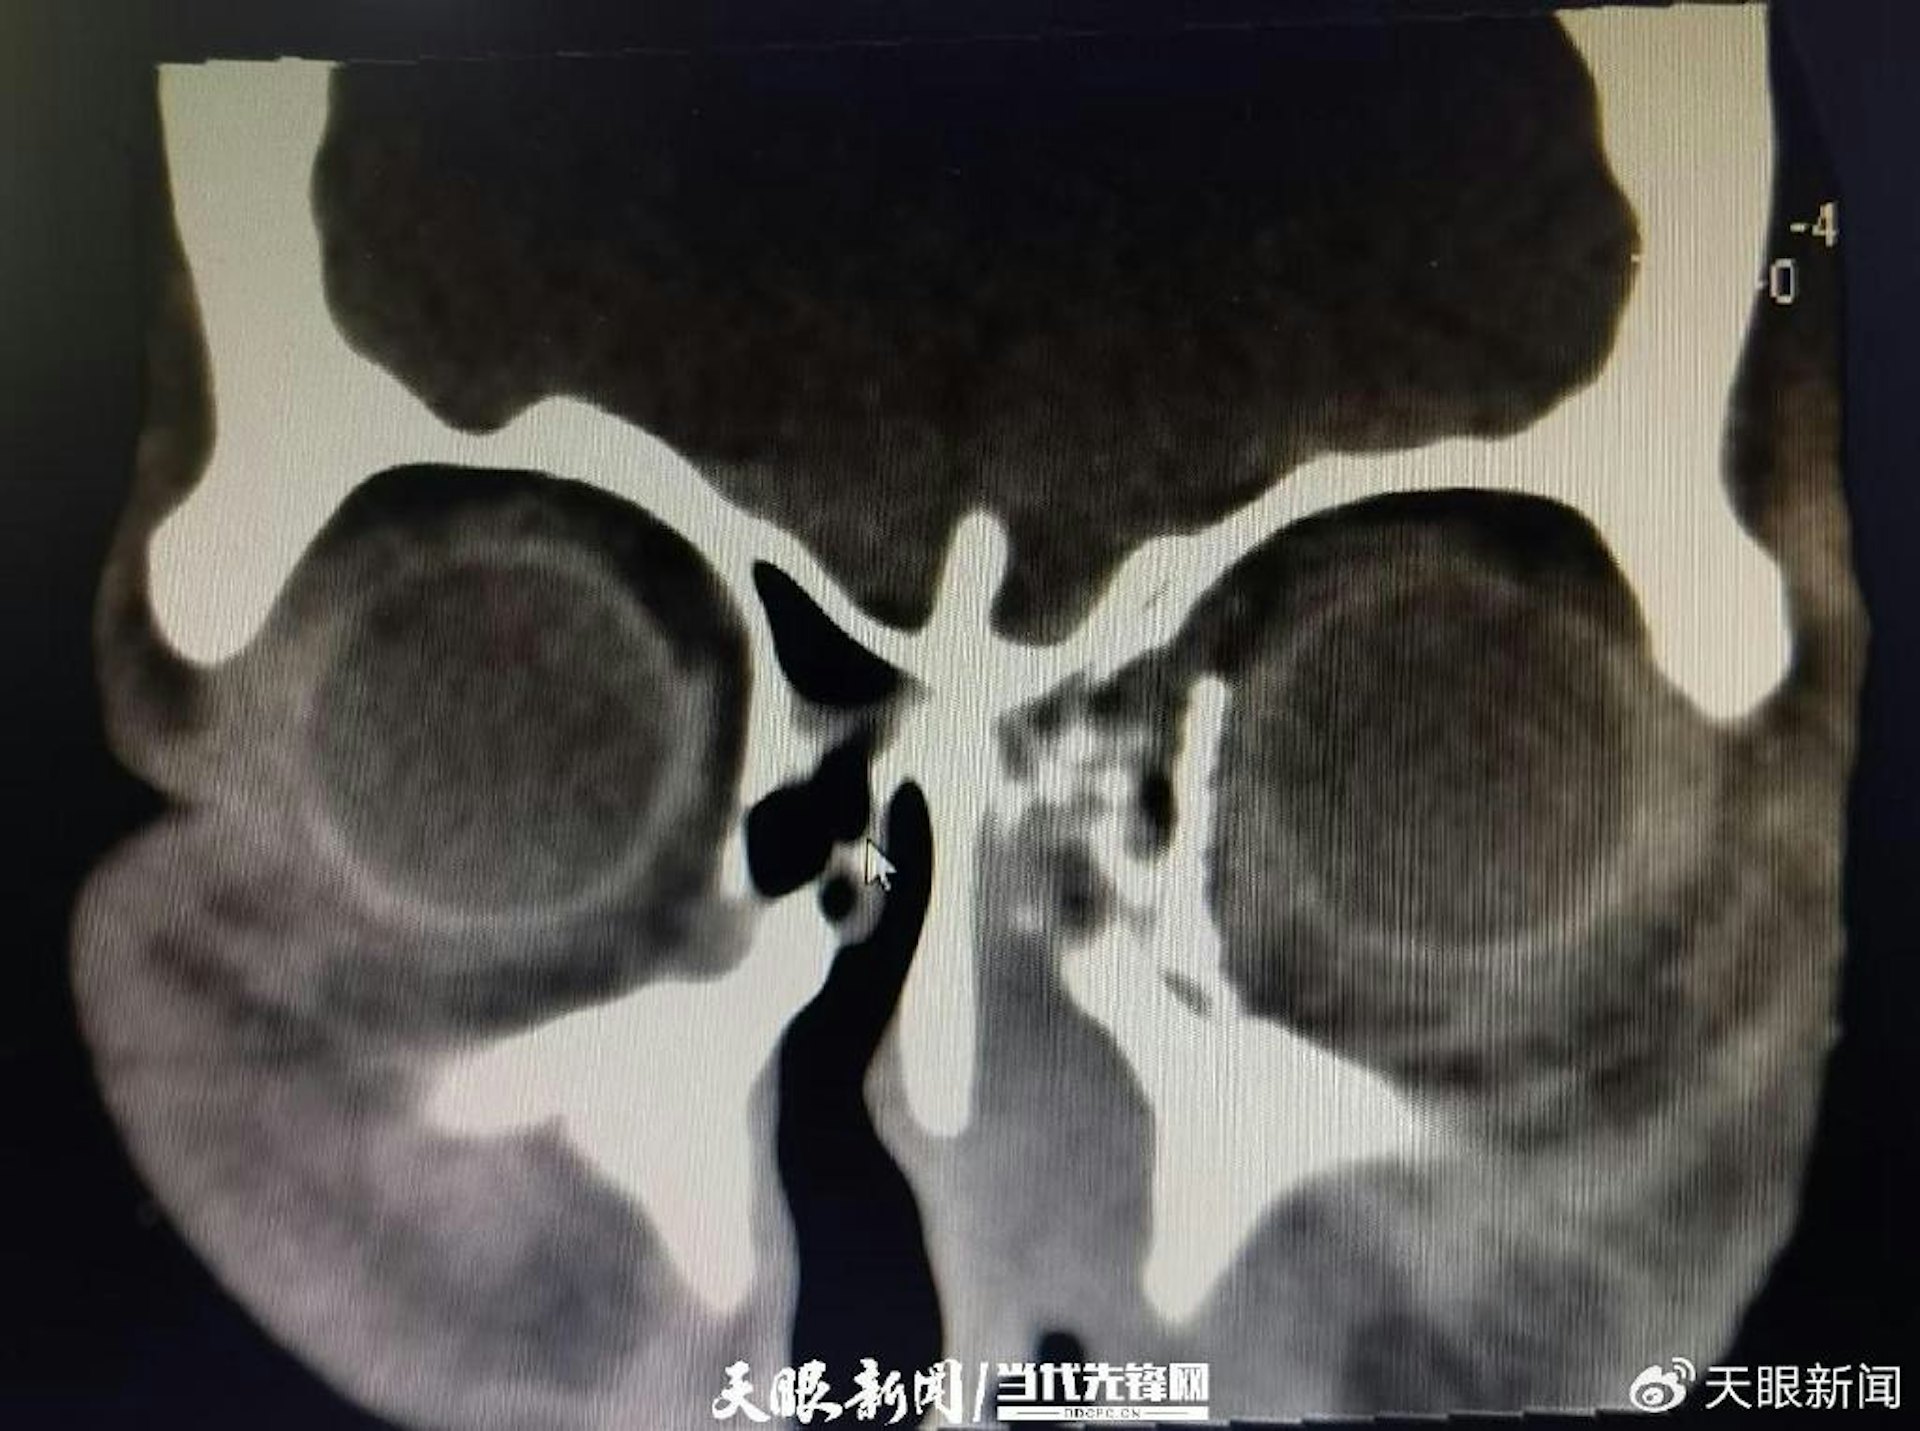

黃女士左眼球脫位並嵌頓於鼻腔內。(天眼新聞)公仔箱論壇' K/ Z. o5 n9 F+ L+ K6 `0 ^2 p8 i

" n n% ]; x8 t5 O+ u- x8 bTVBNOW 含有熱門話題,最新最快電視,軟體,遊戲,電影,動漫及日常生活及興趣交流等資訊。術前CT檢查影像,左眼球掉入眼眶。(天眼新聞)/ z8 f4 U1 y8 _1 L4 Z% @

- X/ p( A, k: [" [& t# T4 e貴州醫科大學附屬醫院眼科副主任醫師楊夏講解,「傷者入院時,我們檢查發現其左眼眶和眼球在高墜傷中受到嚴重衝擊,導致左側眼眶內側壁及眼眶下內側壁爆裂性骨折,眼球脫位嵌頓入鼻腔內卡於左側篩竇內和上頜竇內上方,眼球周圍佈滿骨折碎片,眼球變性並且視神經扭曲……」,經仔細查看影像學資料,考慮到傷者受傷時間不到48小時,越早將嵌頓的眼球復位到眼眶內,才有搶救左眼視功能的可能性,於是決定立即為其進行緊急手術搶救傷眼。